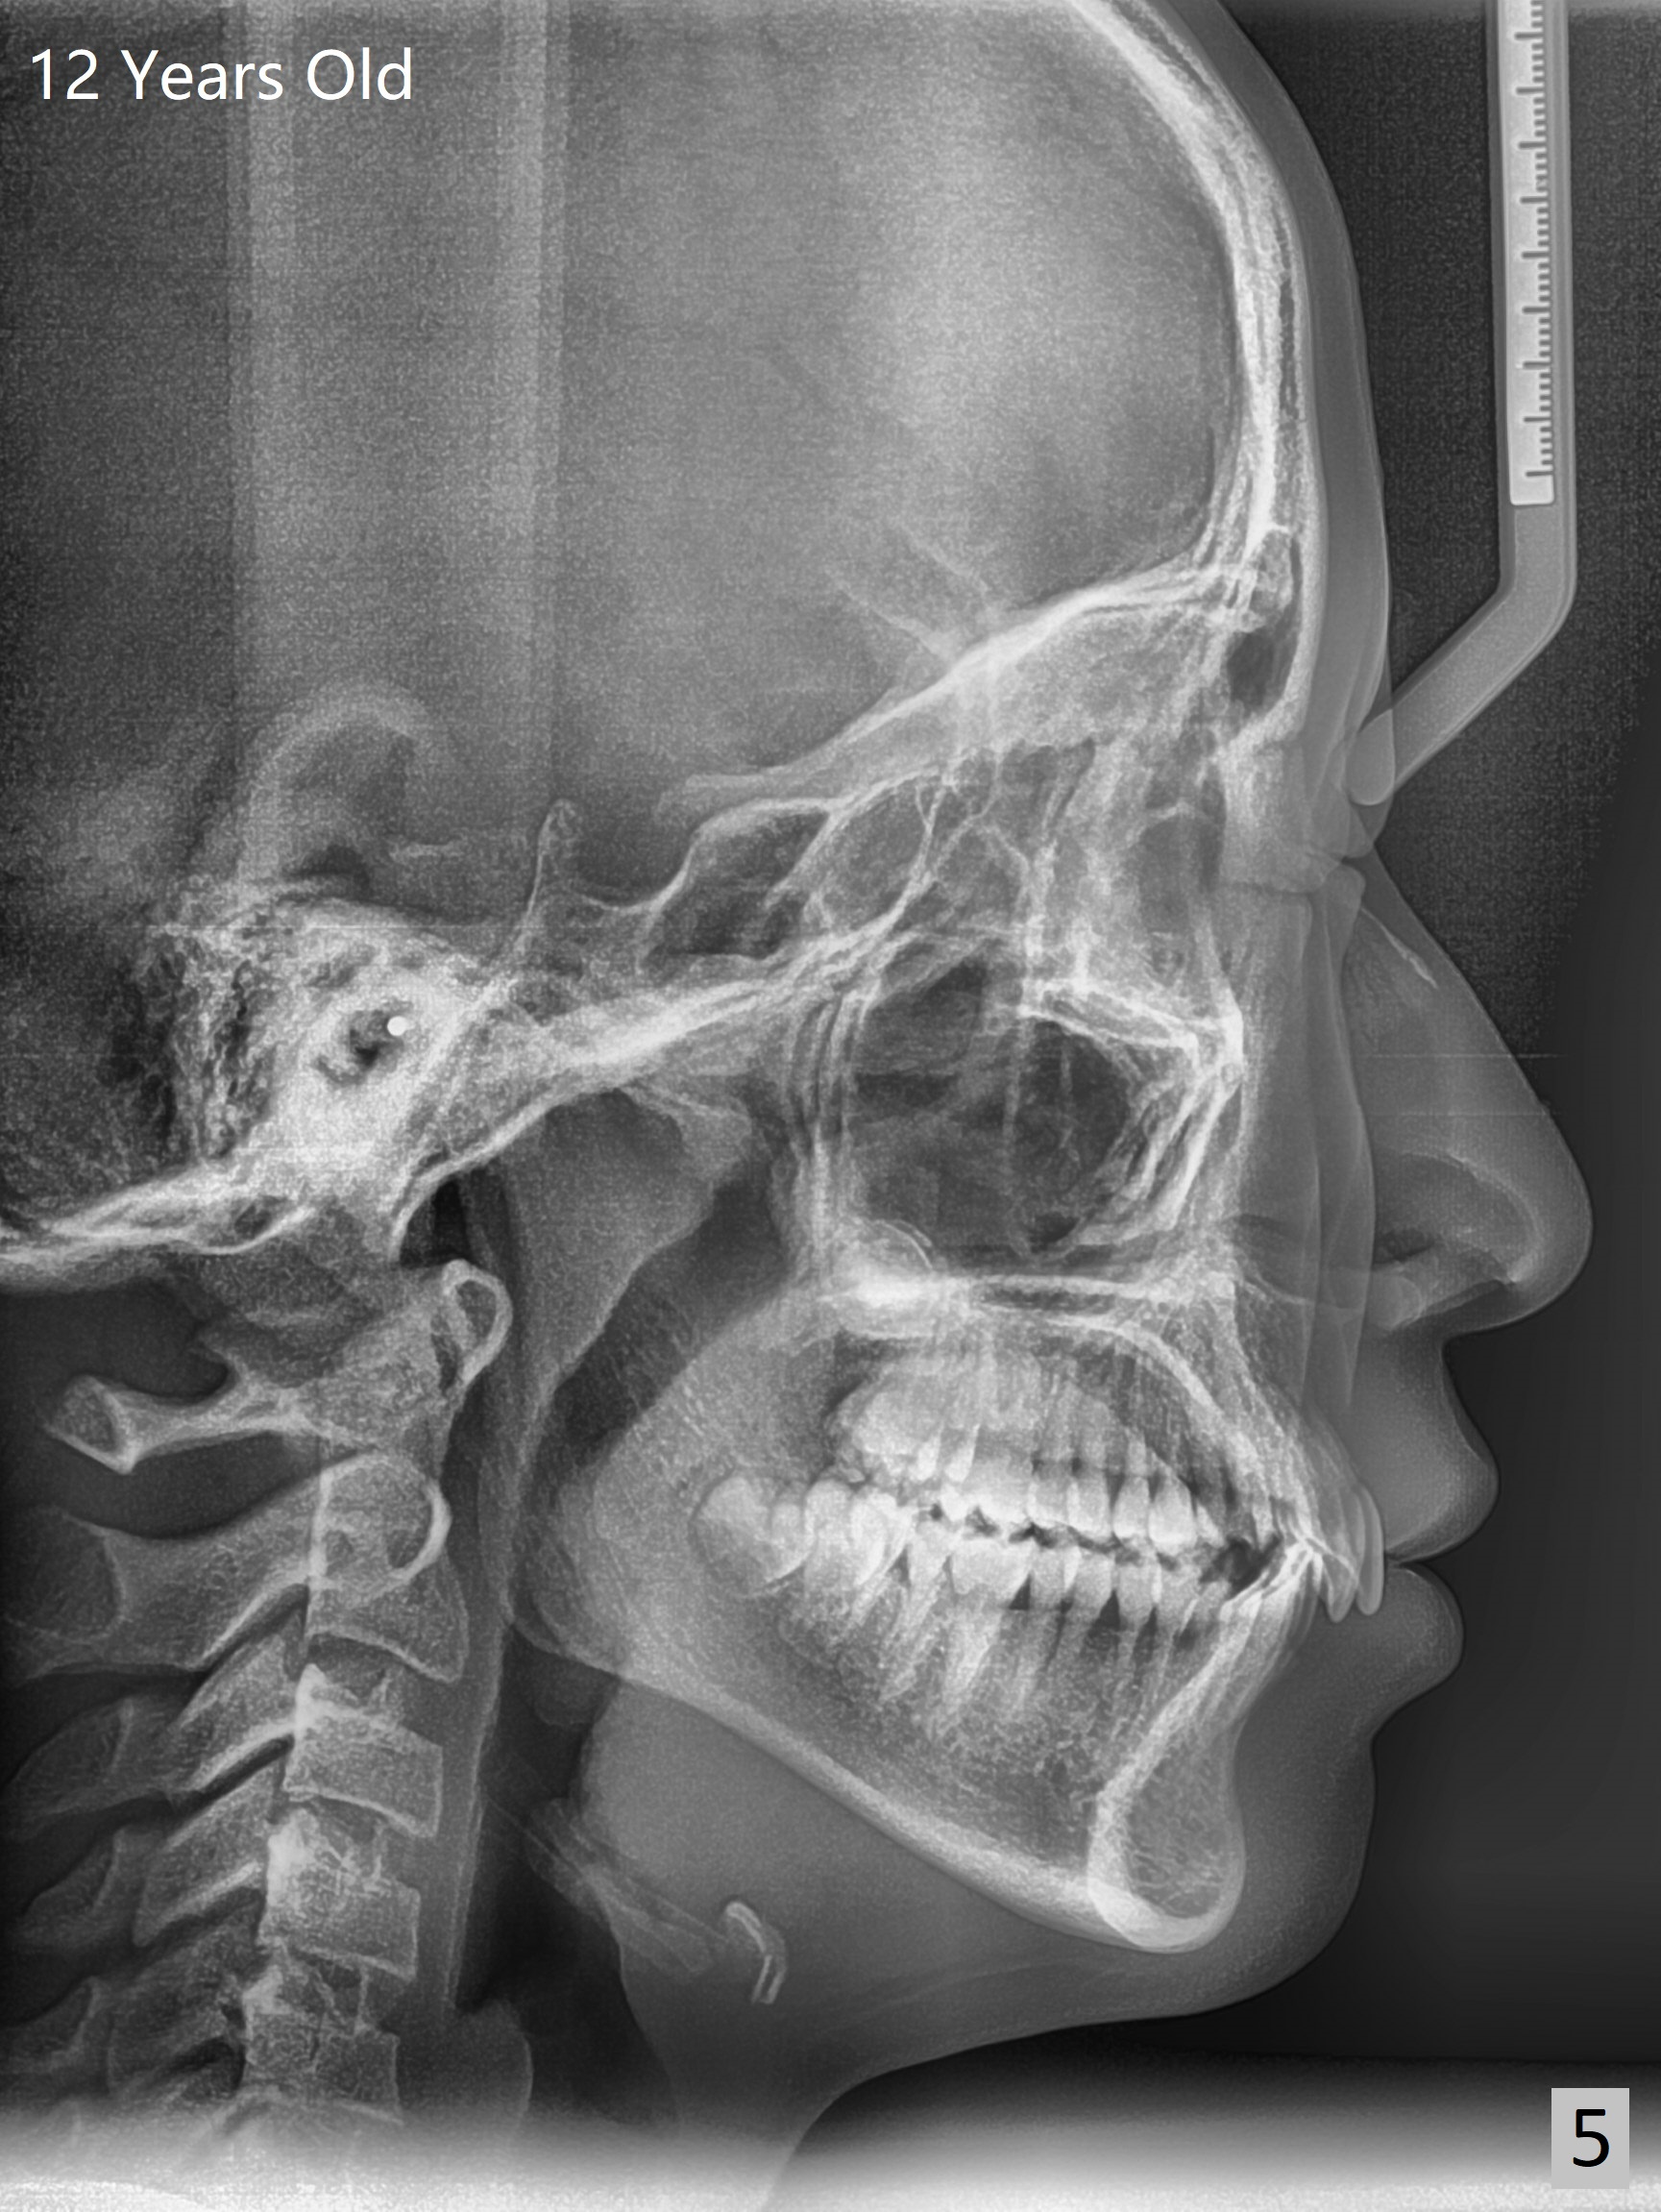

A 12-year-old woman has normal facial profile (Fig.1-6,12) and crowded dentition (7-11). Because of erupting 2nd molars (Fig.10,15), it is difficult to place rubber separators between U6/7. Copper ones are used instead (Fig.15 ^). Crowding and narrow arches (Fig.13,14) may be associated with the enlarged right Inferior Nasal Concha (Fig.15 *).